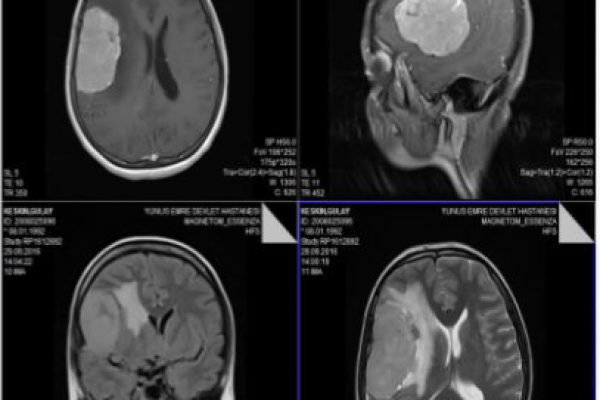

ATİPİK MENENGİOMA

Beyin tümörü ameliyatları ne olursa olsun cerrah için zordur. Her şey yolunda gitse bile, ameliyat sonrası hasta anesteziden uyanana kadar ömründen ömür alır, hasta kolunu bacağını hareket ettirip te bir de konuşmaya başladı mı, dünyalar o saniye için cerraha kalır:)

Gülay 24 yaşında, yeni evli. Eşi ile bana ilk geldiğinde, ameliyat olacağını duyunca ilk sorduğu soru çocuğum olabilecek miydi…Ameliyat perşembe günü yapıldı, bugün 2 gün hastanede kaldıktan sonra evine gidiyor, artık çocuğuyla el öptürmeye gelecek söz verdi:)